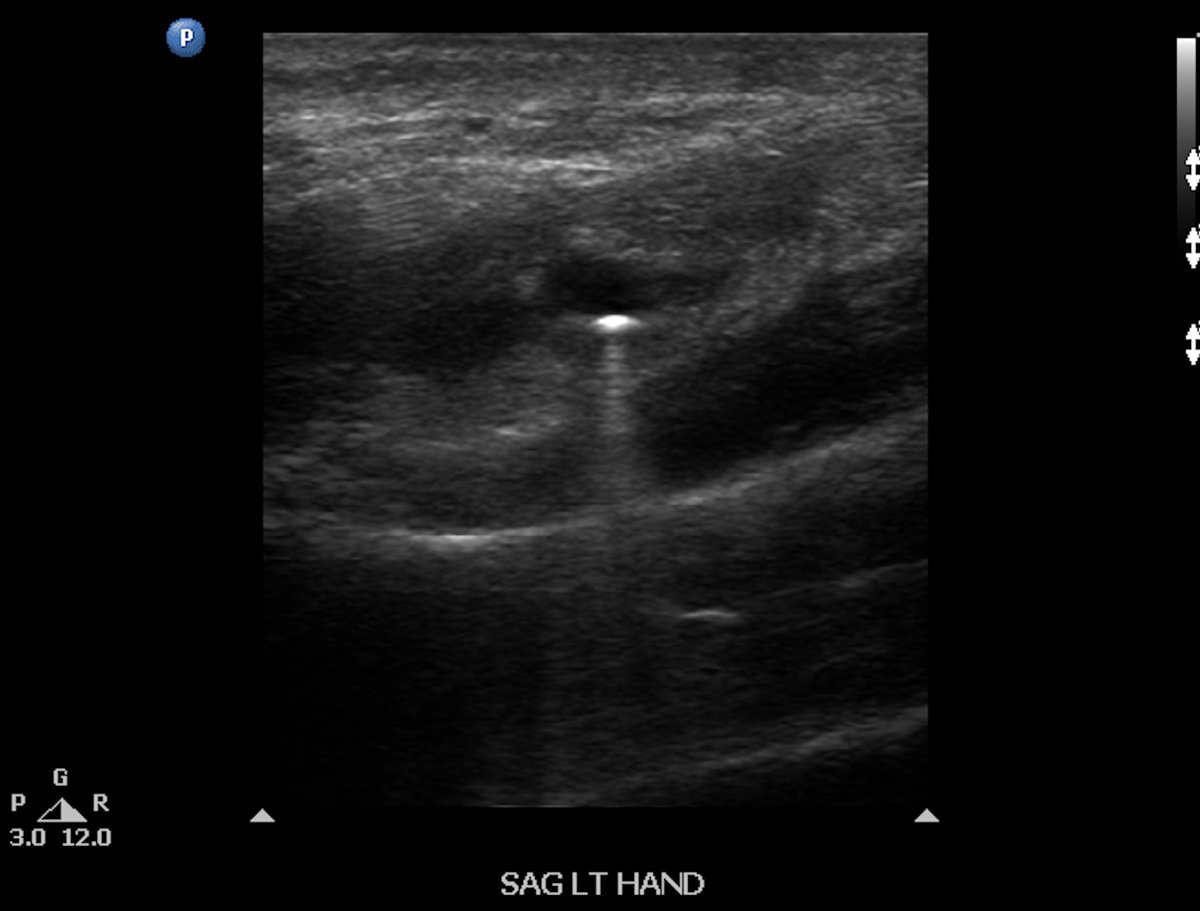

Acute BB gun injury with retained pellet to hand